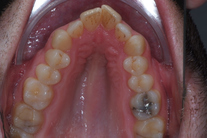

Tandreglering 3

35-årig man med smal och trångställd tandbåge. Vill ha ett jämnt leende. Behandling bestod av knappt 9 månader med genomskinliga Invisalignskenor.